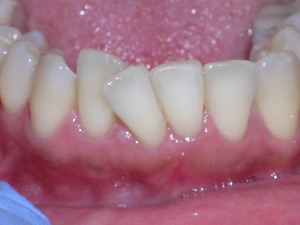

Here’s an example from a woman who had very significant crowding. There was a missing tooth on the bottom right. We considered extracting three other teeth, but decided not to.

Instead we decided to do braces and treat on a non extraction basis with trimming or shaving between teeth to create additional space.

We placed braces and begun a process of trimming or narrowing select teeth. Note that it is a painless procedure, and no anesthesia was needed.

Here are the results.